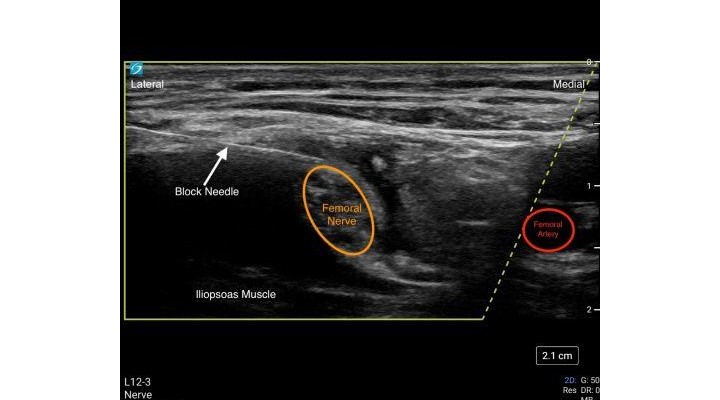

- Begin by placing the transducer transversely in the inguinal crease to identify the Common Femoral Artery.

- The Femoral Nerve is identified lateral to the Common Femoral Artery.

- Use the in-plane needle technique with a lateral to medial approach.

- Initial injection of local anesthetic occurs lateral to the Femoral Nerve.

- The block needle is repositioned to ensure deposition of local anesthetic around the Femoral Nerve.

- The Femoral Nerve is surrounded by the Fascia Iliaca. Initial Injection should occur just adjacent and lateral to the Femoral Nerve within the surrounding Fascia Iliaca.

- Injection of local anesthetic will allow the Femoral Nerve to be easily identified as it is displaced by the injection. The Femoral Nerve will become round in appearance after injection.